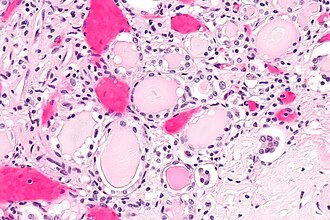

End-stage kidney with thyroidization. H&E stain. | |

| LM | global sclerosis of the glomeruli, interstitial fibrosis, +/-thyroidization (colloid-like hyaline cast formation that impart an appearance that mimics the thyroid gland) |

- Global sclerosis of the glomeruli.

- Interstitial fibrosis.

- +/-Thyroidization - colloid-like hyaline cast formation that impart an appearance that mimics the thyroid gland:[2]

- Typical of chronic pyelonephritis and obstructive nephropathy.